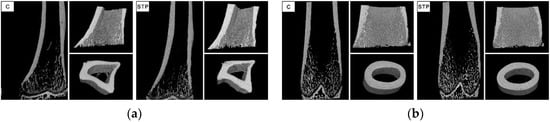

2.5. Micro X-ray Computed Tomography

- Bouxsein, M.L.; Boyd, S.K.; Christiansen, B.A.; Guldberg, R.E.; Jepsen, K.J.; Muller, R. Guidelines for assessment of bone microstructure in rodents using micro-computed tomography. J. Bone Miner. Res. 2010, 25, 1468–1486. [Google Scholar] [CrossRef] [PubMed]